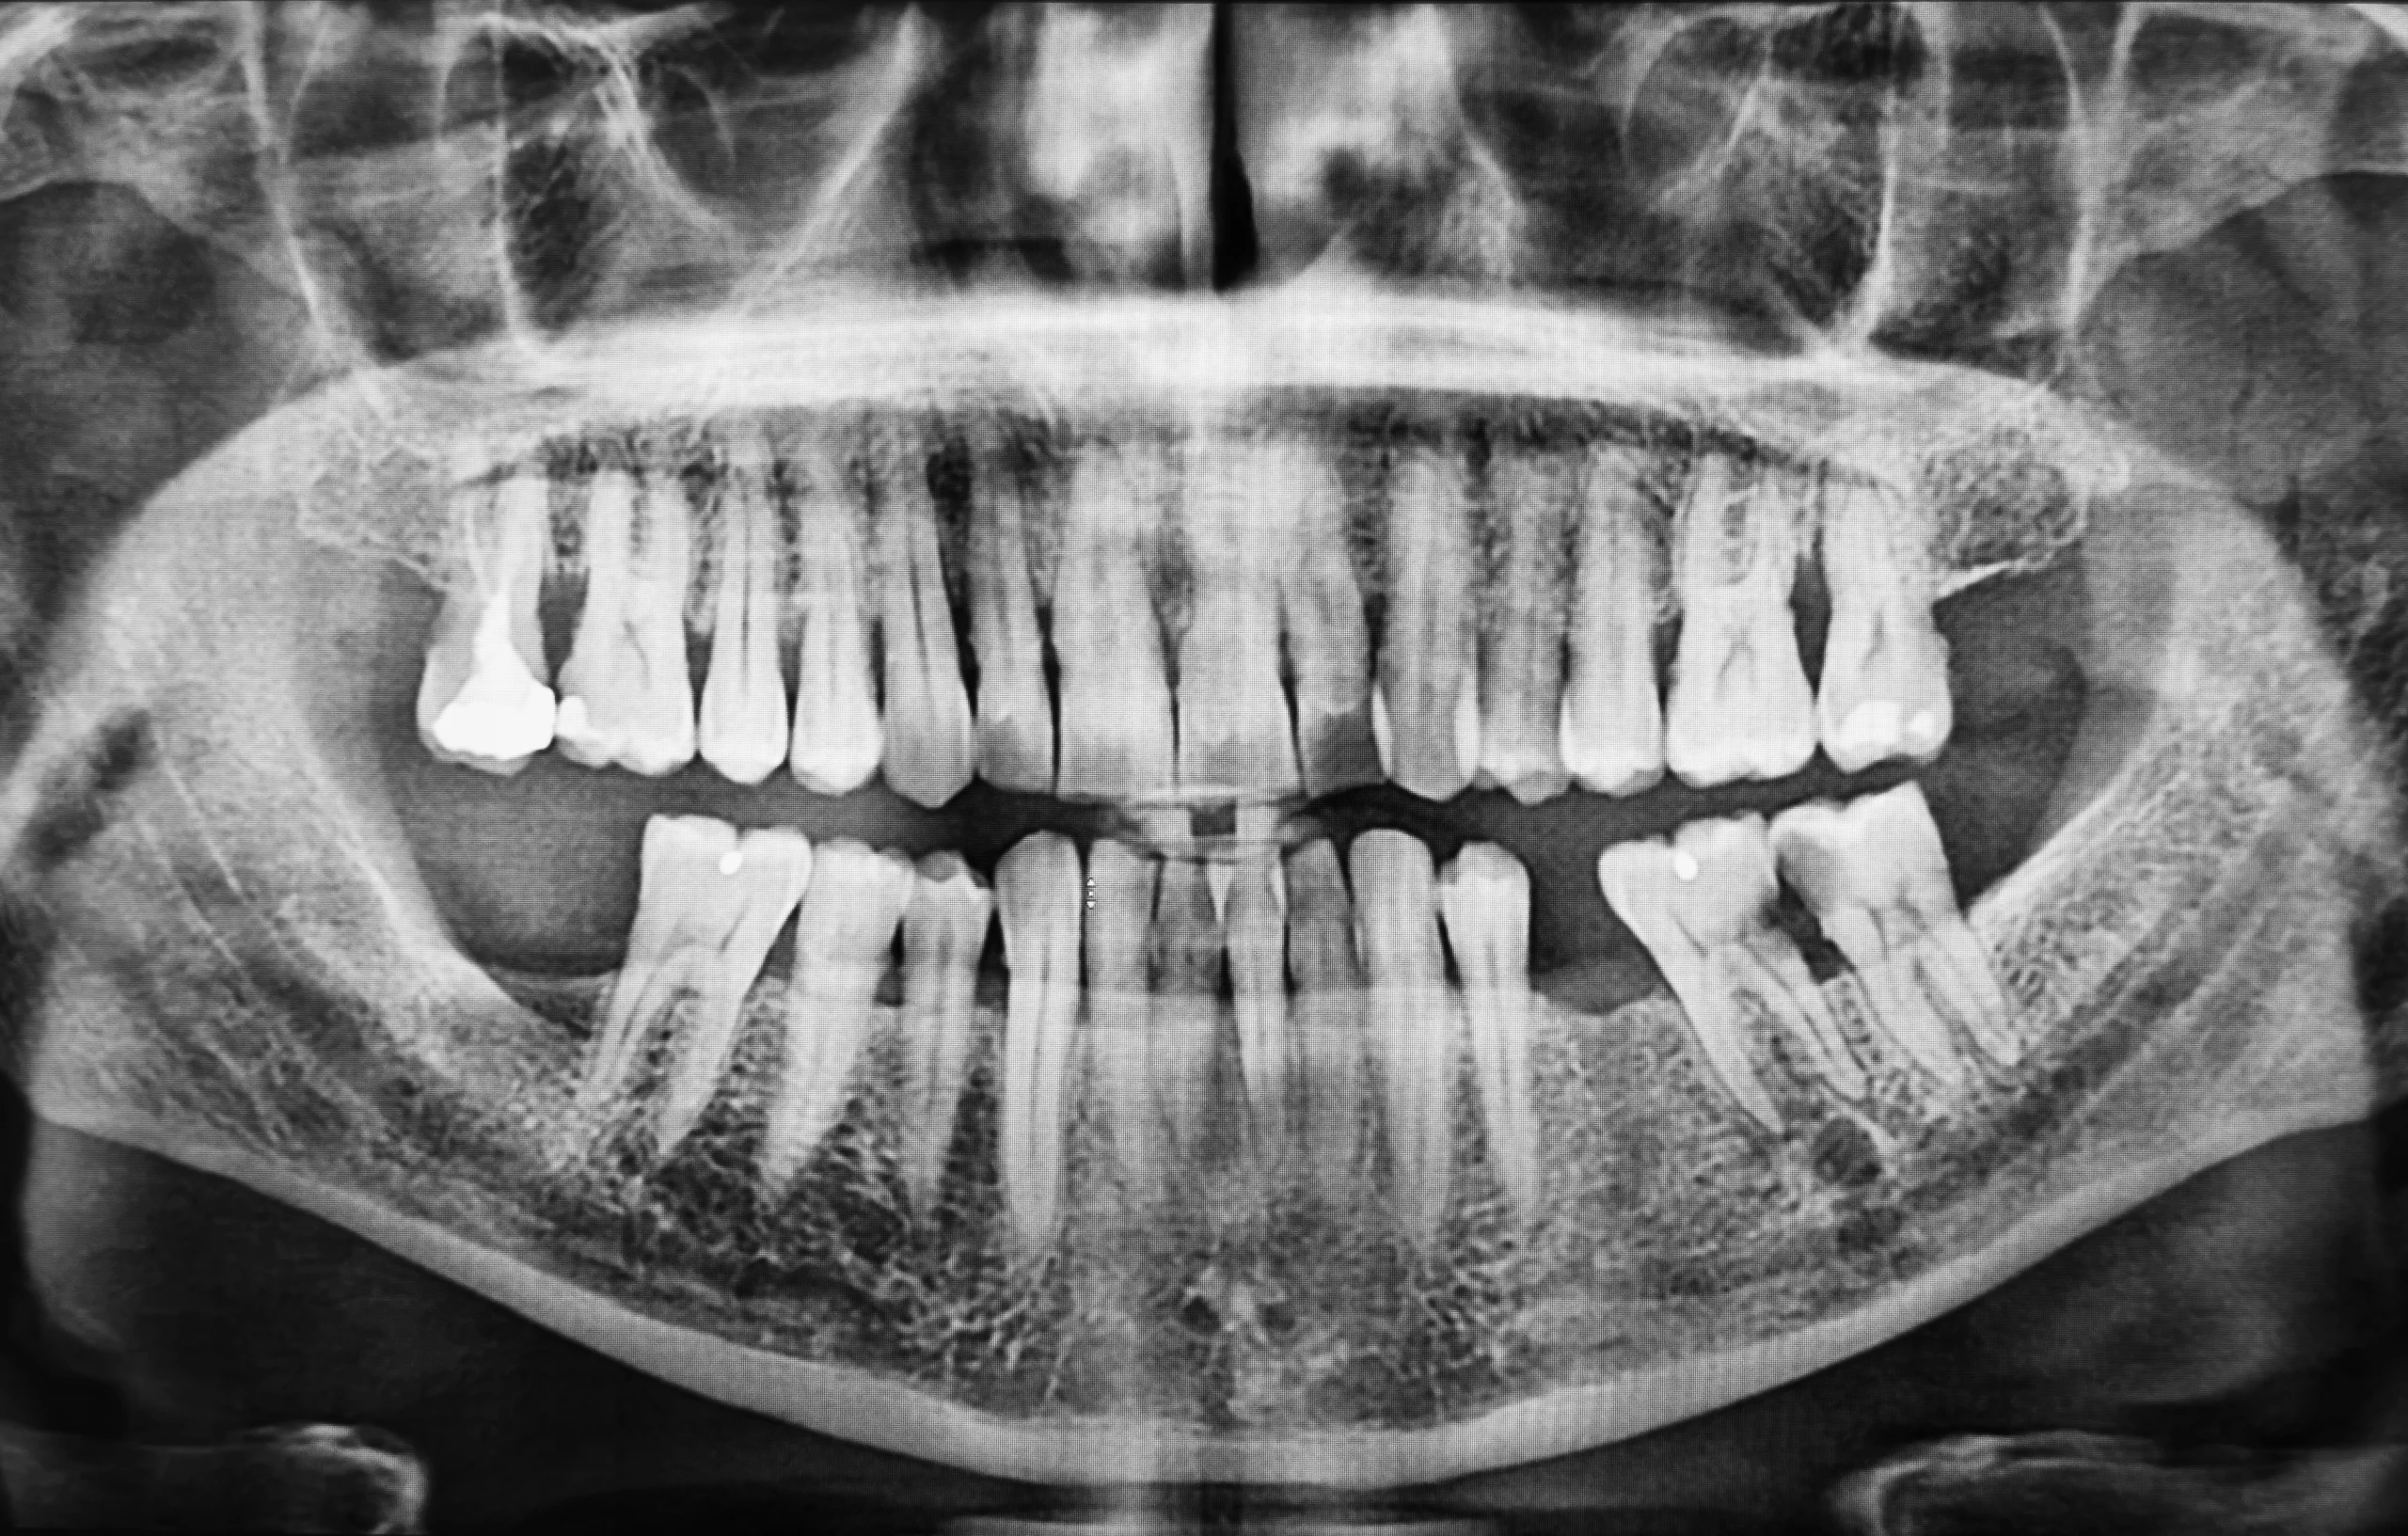

What the CT or CBCT Scan Shows Before Implant Surgery

A CT or CBCT scan helps the clinician evaluate bone shape, bone volume, and the three-dimensional relationship between the planned implant site and nearby anatomical structures. Depending on the case, this may include attention to nerve pathways, sinus areas, root positions, or other anatomical limits that are harder to assess on flatter two-dimensional imaging alone.

For patients, this kind of visibility can make the treatment discussion more understandable. Instead of hearing only that an implant is possible, you can better understand whether bone availability is adequate, whether there are anatomical restrictions, and why the implant may need to be placed in a certain way.

That does not mean every case follows the same imaging pathway or that every patient needs the same level of scanning. The decision to use CT or CBCT imaging depends on the clinical situation, the treatment objectives, and the judgment of the implant team.